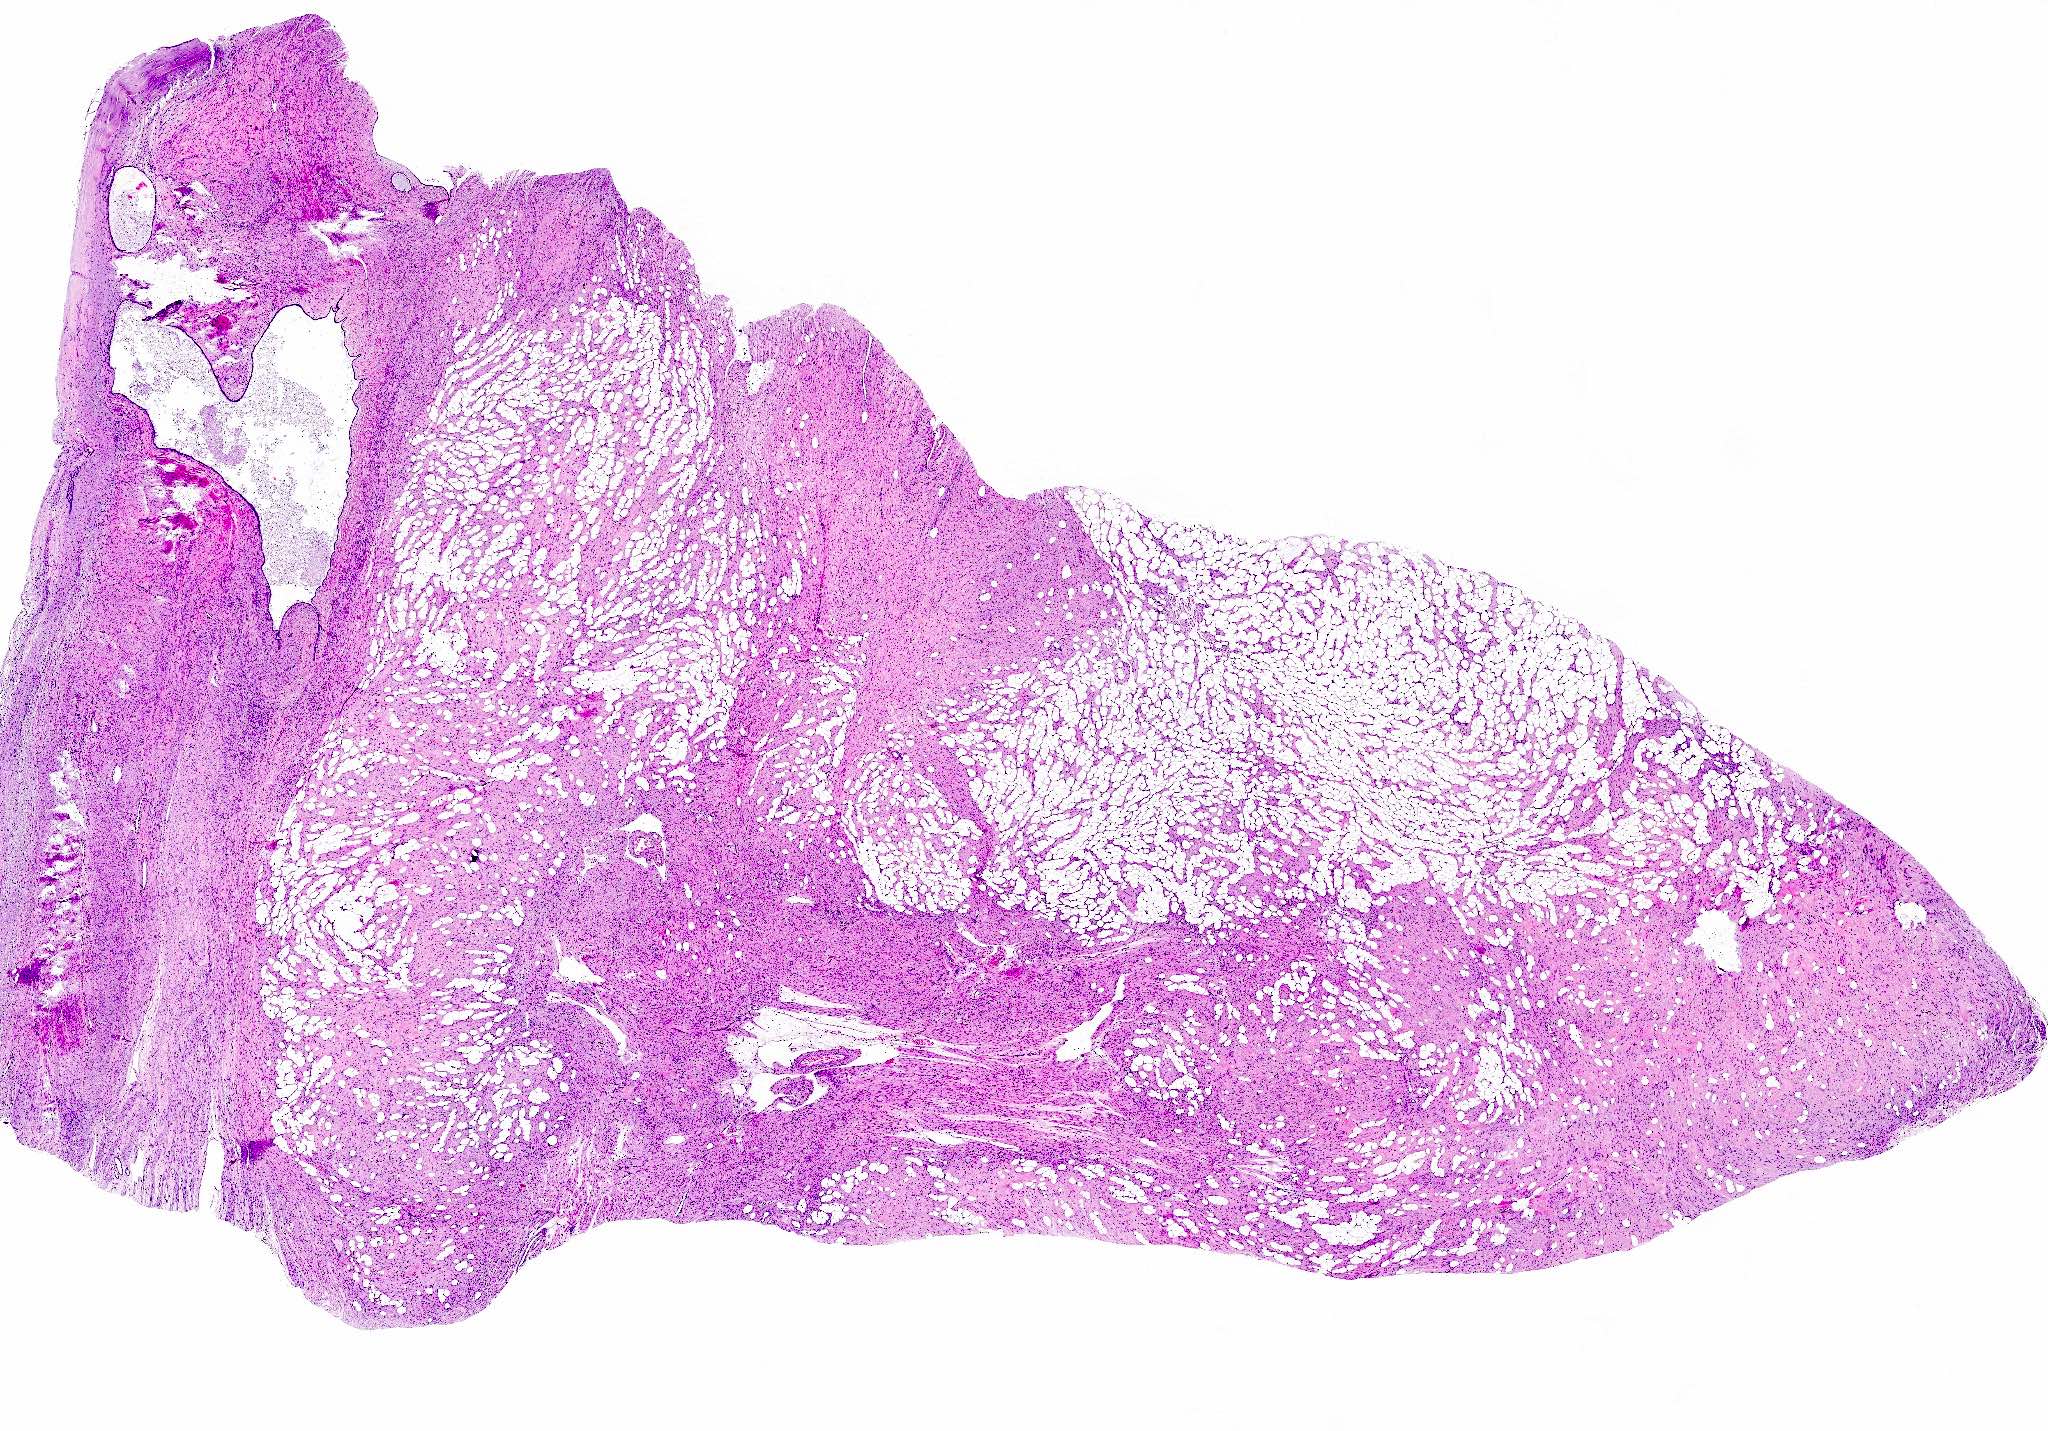

- Lipoleiomyoma:

- Tumor composed of smooth muscle cells mixed with mature adipocytes (variable quantity)

Microscopic (histologic) images

Contributed by Sabrina Croce, M.D., Ph.D., Kristina Doytcheva, M.D., Jennifer A. Bennett, M.D. (Case #508) and @Andrew_Fltv on Twitter